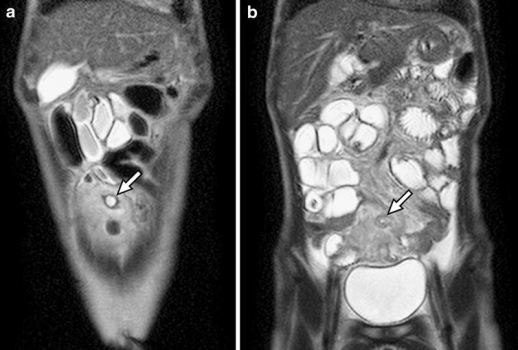

Nhạy hơn về những những thay đổi viêm ở vùng quanh túi thừa Meckel. Nếu có lạc chỗ niêm mạc tuyến dạ dày thì lớp này sẽ hiện rõ do bắt thuốc cản từ ngay lập tức ở thì mao mạch (Capillary phase) và thì mô kẽ (interstitial phase).

Hình 6: Hình T1W xóa mỡ sau tiêm thuốc cản từ, túi thừa Meckel có dạng hình giọt nước (mũi tên). Lớp trong bắt thuốc cản từ mạnh hơn lớp niêm mạc của đại tràng và hồi tràng, đó là lớp niêm mạc dạ dày lạc chỗ. (Diego R. Martin, Ersan Altun, Jorge Elias et al (2010). Gastrointestinal tract. In: Richard C. Semelka. Abdominal – pelvic MRI 3rd

edition.Wiley-Blackwell: P774)

Hình 7: Hình coronal T2W SSTSE (Single – short turbo spine-echo) cho thấy cấu trúc hình ống có đầu tận cùng nằm giữa dưới rốn, chứa đầydịch (mũi tên). Mỡ mạc treo có tín hiệu không đồng nhất do viêm. (Shilpa Hegde. Jonathan R. Dillman. Samir Gadepalli et al (2012). MR enterography of perforated acute Meckel diverticulitis. Springer Pediatr Radiol 42:259).